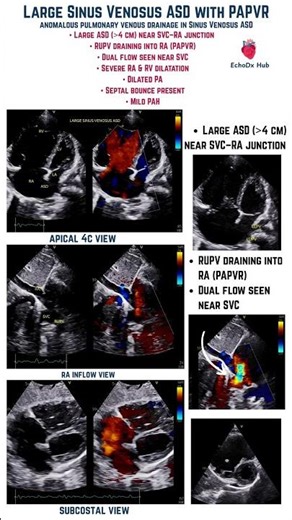

- Echo of ASD

ASD On Cho - ASD